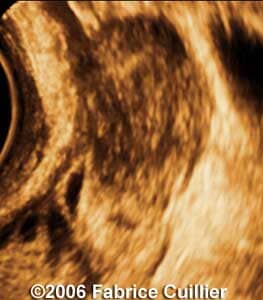

These are some cases of ectopic pregnancy (GEU) using the 2D and 3D scans.